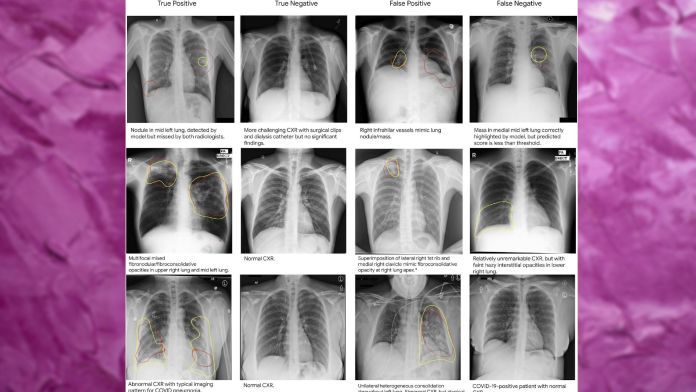

Học sâu có thể phát hiện các mảnh X-quang ngực bất thường với độ chính xác ngang bằng với các chuyên gia chẩn đoán hình ảnh chuyên nghiệp, theo một bài báo mới của một nhóm nghiên cứu trí tuệ nhân tạo tại Google, được công bố trên tạp chí khoa học đồng nghiệp Nature.

Hệ thống học sâu có thể giúp các chuyên gia xem mảnh X-quang ngực ưu tiên, đồng thời có thể phục vụ như một công cụ phản ứng đầu tiên trong các tình huống khẩn cấp nơi chuyên gia chẩn đoán kinh nghiệm không có sẵn. Những kết quả cho thấy rằng, trong khi học sâu chưa thể thay thế các chuyên gia chẩn đoán hình ảnh, nó có thể giúp tăng cường năng suất của họ trong bối cảnh thế giới đang đối mặt với tình trạng thiếu hụt nghiêm trọng về các chuyên gia y tế.

Trong bài báo của họ, các nhà nghiên cứu Google lưu ý rằng mô hình học sâu của họ đã thành công trong việc phát hiện ảnh X-quang bất thường với độ chính xác có thể so sánh và đôi khi vượt trội so với bác sĩ chuyên khoa hình ảnh. Tuy nhiên, họ cũng chỉ ra rằng lợi ích thực sự của hệ thống này là khi nó được sử dụng để cải thiện năng suất của bác sĩchuyên khoa hình ảnh.

Để đánh giá hiệu suất của hệ thống học sâu, các nhà nghiên cứu đã thử nghiệm nó trong hai kịch bản mô phỏng, trong đó mô hình hỗ trợ bác sĩ chuyên khoa hình ảnh bằng cách giúp ưu tiên quét ảnh được xác định là bất thường hoặc loại bỏ quét ảnh được xác định là bình thường. Trong cả hai trường hợp, sự kết hợp của học sâu và bác sĩ chuyên khoa hình ảnh đã mang lại cải thiện đáng kể về thời gian xử lý.